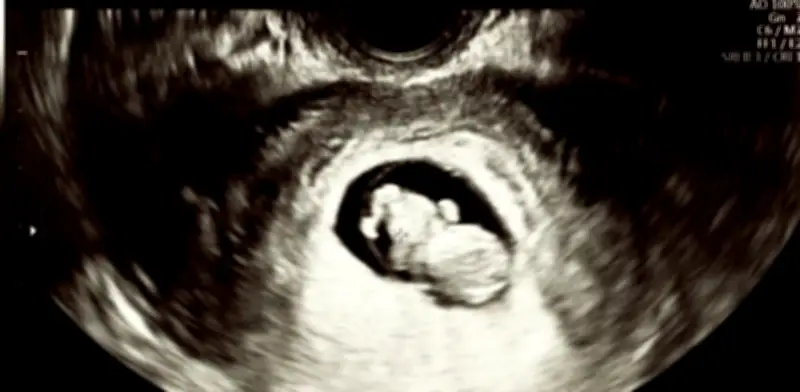

El Gobierno de Puerto Rico ha marcado un hito histórico en el ámbito jurídico y social con la ratificación de una ley que otorga formalmente el estatus de persona al ser humano concebido no nacido. Esta decisión trascendental, impulsada por la gobernadora Jenniffer González, busca elevar la protección del ser humano en gestación a rango constitucional, garantizando así plenos derechos de amparo frente a cualquier acto de violencia.

La trascendencia de esta legislación se subraya con la enmienda directa al Código Penal, la cual tipifica como asesinato la muerte de un no nacido ocurrida en incidentes de agresión dirigidos contra la mujer gestante. Esta medida pretende no solo castigar con mayor rigor los crímenes, sino también establecer un estándar de justicia que reconozca la existencia de dos víctimas en actos de violencia contra mujeres embarazadas.

Al armonizar la legislación penal con las reformas del Código Civil aprobadas meses antes, se eliminan las ambigüedades legales que previamente dejaban al no nacido en una posición de vulnerabilidad jurídica. El gobierno puertorriqueño ha reiterado que esta ley responde a un compromiso ético con la coherencia legal al otorgar personalidad jurídica al no nacido.